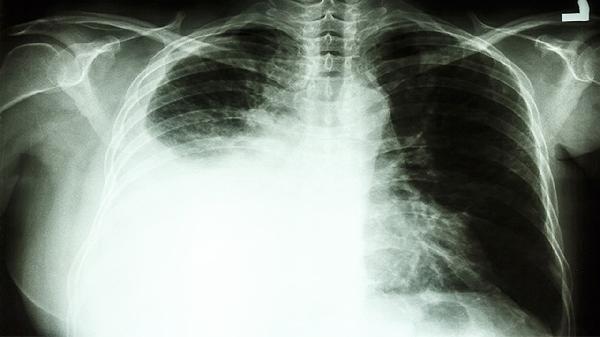

1、肺脓肿与肺癌的关系:肺脓肿是由于细菌感染引起的肺部组织坏死和脓液积聚,通常由肺炎、吸入异物或免疫力低下引发。肺癌则是肺部细胞异常增殖形成的恶性肿瘤,两者的发病机制不同。肺脓肿本身不会直接导致肺癌,但长期未治疗的肺脓肿可能导致肺部组织纤维化或慢性炎症,这些变化可能增加肺部细胞异常增殖的风险。

肺脓肿和肺癌是两种不同的疾病,肺脓肿不会直接导致肺癌,但长期未治疗的肺脓肿可能增加肺部组织受损的风险,间接影响肺部健康。通过早期治疗和预防措施,可以有效降低肺脓肿对肺部健康的影响。建议有肺部不适症状的人群及时就医,进行详细检查和治疗,以保障肺部健康。